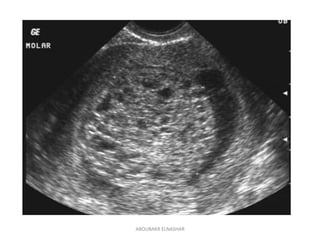

USS findings

Complete mole

• Snowstorm’ appearance of mixed echogenecity,

representing hydropic villi and intrauterine

haemorrhage.

• Large theca lutein cysts.

Partial mole

Fetus may be viable,

with signs of early growth restriction or

structural abnormalities.

USS findings Complete mole •Snowstorm’ appearance of mixed echogenecity, representing hydropic villi and intrauterine haemorrhage. • Large theca lutein cysts. Partial mole Fetus may be viable, with signs of early growth restriction or structural abnormalities. ABOUBAKR ELNASHAR